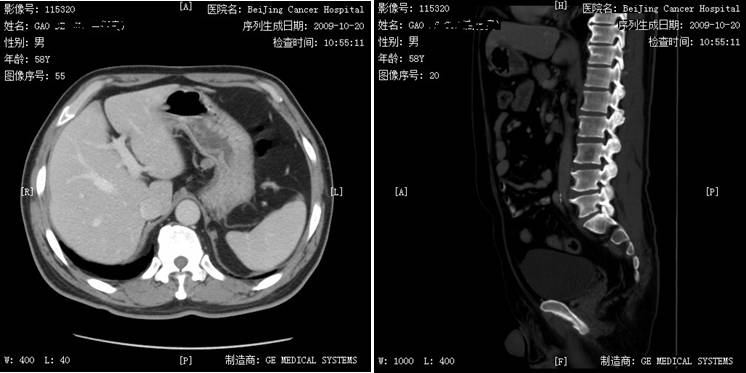

患者于1998年行右肾透明细胞癌术,术后行干扰素治疗1月余,2009年发现双肺多发占位,2009年11月开始口服培唑帕尼800 mg QD治疗。治疗2周期病灶缩小,治疗4周期达疾病稳定(SD),治疗期间出现肝损3度、血压升高、口腔黏膜炎、腹泻1~2度,培唑帕尼减量至600 mg口服治疗,疾病持续稳定。迄今患者术后已累计生存达18年,累计应用培唑帕尼治疗7年,生存状况良好。 姓名:高某 性别:男性 年龄:74岁 患者1998年行右肾透明细胞癌术,术后行干扰素治疗1月余。2009年因憋气/胸闷于石景山医院就诊。2009年10月19日,行胸部增强CT检查发现双肺多发结节,左肺门肿大淋巴结,纵隔小淋巴结,腹部改变,结合病史考虑转移,并建议进一步追查(图1)。2009年10月20日,行腹部CT发现腰3椎体骨转移(图2)。于2009年11月入北京肿瘤医院就诊。既往血糖升高。 图1 2009年10月19日胸部CT检查 双肺纹理走行顺畅,肺内透亮度均匀,双肺见多发大小不等结节,较大约28×23 mm(IMA26),未见肺内结节或斑片影;纵隔4组见小淋巴结,小于10 mm,左肺门见一肿大淋巴结,约26×21 mm(IMA42);锁骨上区及双腋下未见肿大来不及;双侧胸膜稍增厚,未见胸水征象;扫及发现双肺多发占位胸廓诸骨未见明确破坏征象;胃小弯可见一淋巴结,约1 cm(IMA13)。 图2 2009年10月20日腹部CT检查 口服培唑帕尼800mg QD治疗2周期复查病灶有缩小,治疗4周期疗效评价为SD(缩小)。治疗期间患者出现3度肝损伤(最高(ALT221iu/l)、血压升高、口腔黏膜炎、1~2度腹泻。考虑肝损害,予以减量至600mg Qd治疗,未再出现肝转氨酶显著升高,期间出现甲状腺功能减退,甲状腺素替代治疗未诉不适,每3个月复查,疗效评价均为SD。2017年4月21日,体格检查一般情况可,心肺未见异常。肿瘤复查未见增大。 2017年3月复查病灶大致同前,胃小弯淋巴结基本消失,腰3转移消失(图3)。 图3 2017年3月29日复查腹部CT:胃小弯淋巴结基本消失,腰3转移消失 肾透明细胞癌是最常见的肾脏肿瘤,约30%的患者在诊断时已经发生转移。目前晚期肾透明细胞癌的治疗已经是靶向治疗时代,其中主要以酪氨酸激酶抑制剂(TKI)为主,国内先后上市了索拉非尼、舒尼替尼、依维莫司、阿昔替尼、培唑帕尼等,其中,培唑帕尼与舒尼替尼是获得1类循证医学推荐的一线治疗用药,二者在既往的临床Ⅲ期研究中与安慰剂或干扰素相比,均显示了无进展生存(PFS)的获益,并得到了国内外众多指南的一致推荐。对于这两种药物临床如何选择呢?Robert J. Motzer等实施了一项全球多中心临床Ⅲ期随机对照研究,即COMPARZ研究。 该研究自2008年8月至2011年9月在北美、欧洲、澳大利亚和亚洲的14个国家(包括中国)共纳入1110例患者,以1︰1随机分组,分别给予培唑帕尼800 mg/d连续治疗(557例)或舒尼替尼4/2方案(4周50 mg/d,停药2周,553例)。结果显示,培唑帕尼的PFS非劣于舒尼替尼,研究者评审的中位PFS为:10.5个月和10.2个月。两组OS相当,培唑帕尼和舒尼替尼组分别达28.4个月和29.3个月,而培唑帕尼组的肿瘤应答率显著更高。与培唑帕尼组相比,舒尼替尼组患者有更高的疲劳(55%对63%)、手足综合征(29%对50%)和血小板减少症(41%对78%)发生率;而培唑帕尼组患者的丙氨酸氨基转移酶(ALT)水平升高率则高于舒尼替尼组(60%对43%)。在治疗前6个月14种健康相关生活质量较基线的比较中,培唑帕尼组有11种有显著优势,尤其是在疲劳或口腔、喉咙、手或足疼痛等方面,给患者带来了更高的生活质量和治疗满意度。该研究最终结果于2013年在《新英格兰医学杂志》发表,从而改写了晚期肾癌的临床治疗实践。 对于晚期肾癌的总体预后,靶向治疗的中位总生存时间为26-30个月左右,通常一线靶向药物治疗时间为1年左右,对于肺转移患者可以延长至2年左右,而该患者进入COMPARZ研究接受培唑帕尼治疗,持续接受培唑帕尼治疗迄今已累计治疗7年余,疗效评估持续维持缩小的SD,肿瘤获得良好的控制,生活质量良好,证实了培唑帕尼在临床实践中的良好疗效。也为肾透明细胞癌患者的临床一线靶向药物选择提供了有力的参考。 盛锡楠教授 副主任医师,副教授,硕士研究生导师,北京大学肿瘤医院肾癌黑色素瘤内科副主任。长期从事肿瘤内科临床和科研工作,擅长肾癌、膀胱癌、前列腺癌等泌尿肿瘤以及黑色素瘤的内科治疗。担任《中国肾癌诊治指南?2015版》执笔人,CSCO青委、CSCO肾癌专家委员会秘书,中国抗癌协会泌尿男生殖肿瘤专业委员会青委,北京抗癌协会泌尿男生殖肿瘤专业委员会委员兼秘书,CGOS分子靶向分委会常委。病例摘要